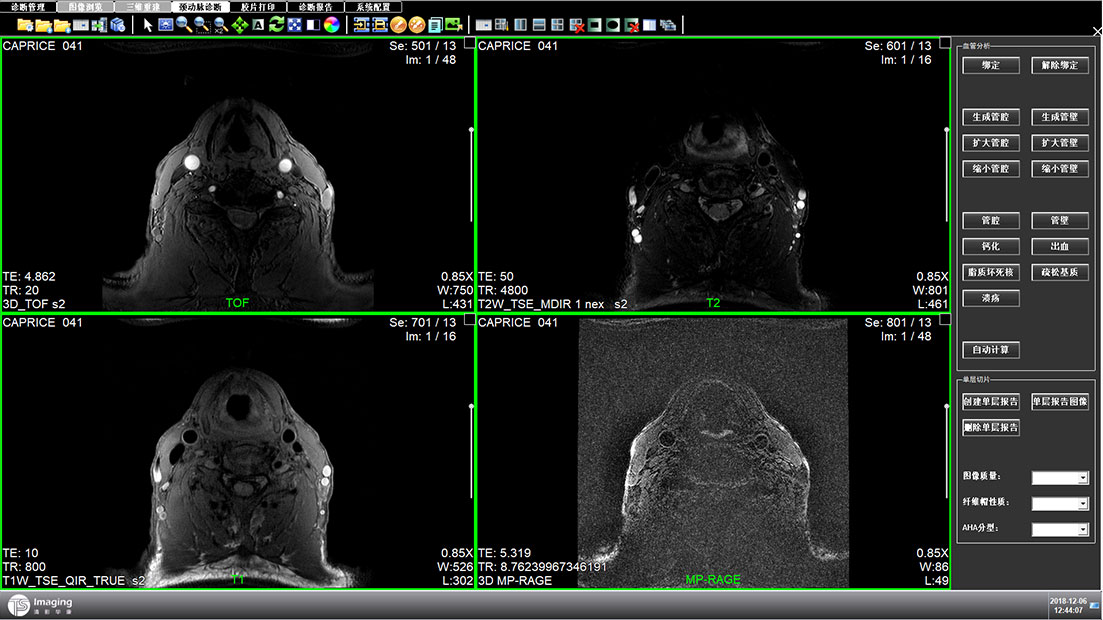

頸動脈診斷頁面

頸動脈診斷頁面整體布局和三維重建比較相似,最大的區別是右側的操作區域,血管分析都為按鍵操作,通過間隔的大小分成三部分。單層切片除了按鍵還有下拉菜單的操作。